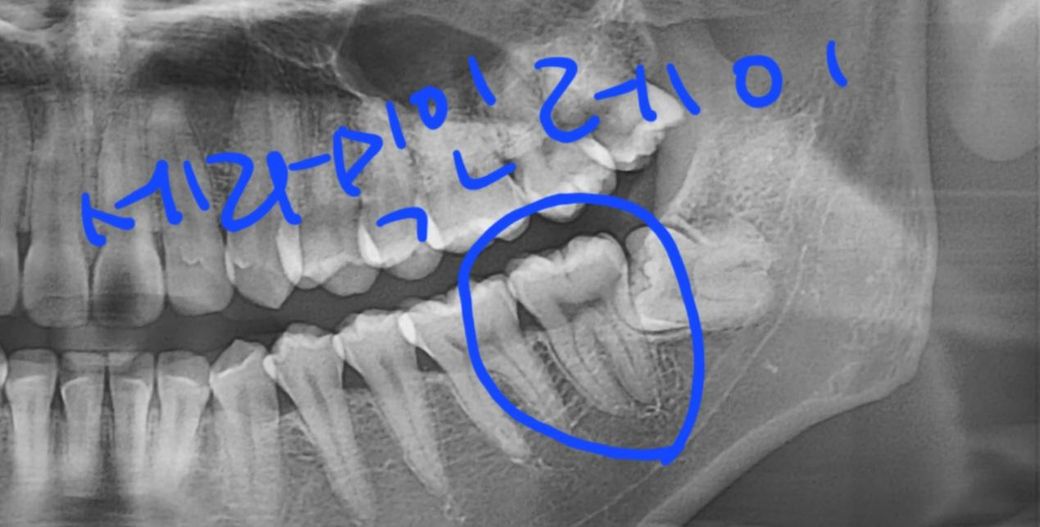

깨진 윗어금니 발치,시린 아래어금니 레진 가격

위에 얘기를 하고 상태를 보시더니 깨진 윗어금니와 그 뒤에있는 사랑니 두개는 발치해야하고 아래 시린 어금니는 레진으로 하자고 하셨는데 레진비용이 40만원이고 발치비용은 본인부담보험이라 써져있고 다른 심하게 썩은 이가 또 있어 이건 세라믹 인레이로 하자고 하셨는데 이건 54만원이 적혀있습니다.

깨진게 심해서 발치를 하자고 하셨는데 깨진게 심하면 크라운은 못하나요??

제가 삼십대라 최대한 이를 살려 크라운으로 하고싶은데 진짜 이가 많이 깨져있으면 크라운은 못하는건가요??

사진상으로는 염증이 안보이나요..?

치아 뿌리쪽에는 염증이 없지만 구강내 사진에는 치아 주변이 발적되면서 잇몸에 염증이 잇는 상태입니다. 치아 깨진게 상당히 넓고 깊어 보여서 저정도면 크라운 치료를 해야될것같습니다.

깨진게 심해서 발치를 하자고 하셨는데 깨진게 심하면 크라운은 못하나요?? -> 엑스레이 사진이나 임상사진봐도 깨진 치아는 살리기 쉽지 않아 보입니다